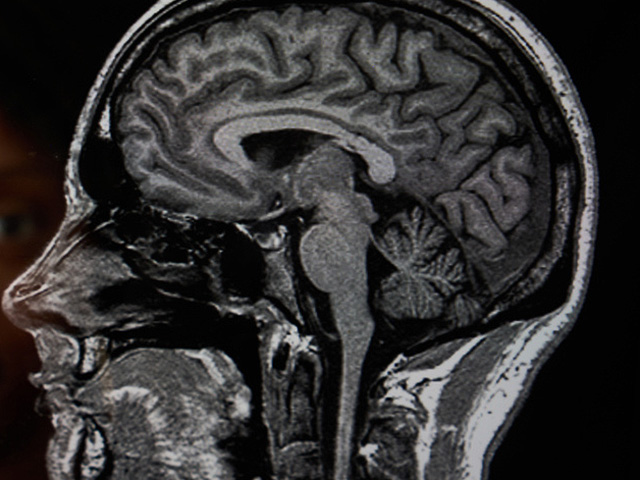

Первые тревожные изменения в поведении сына Фэрбэрн заметила вскоре после своей свадьбы с отчимом Андре, Аластером, в ноябре 2022 года. Молодой человек стал более рассеянным и иногда вел себя неадекватно. Обследование в университетской больнице Норфолка и Норвича выявило необычное уменьшение объема мозга, а окончательный диагноз был поставлен в больнице Адденбрука в Кембридже.